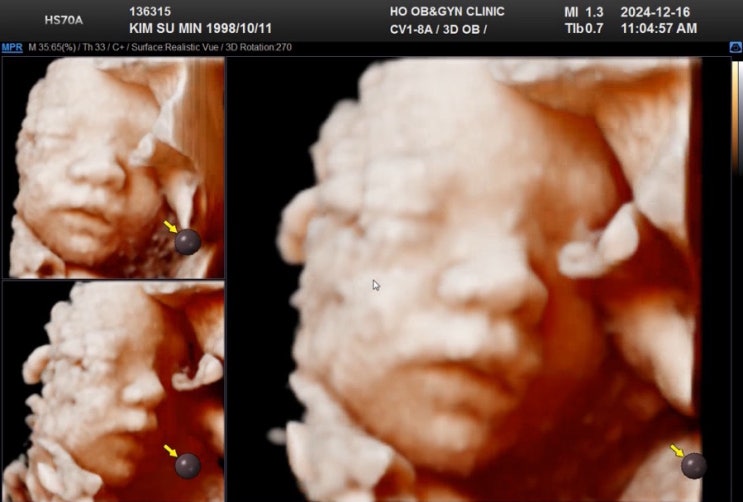

26w5d 춘천 호산부인과 임당검사/입체초음파 후기

드디어 임당검사!! 임당검사 날이 다가올 수록 은근한 압박감이... 임당은 호르몬 영향이라지만 원체 건강...